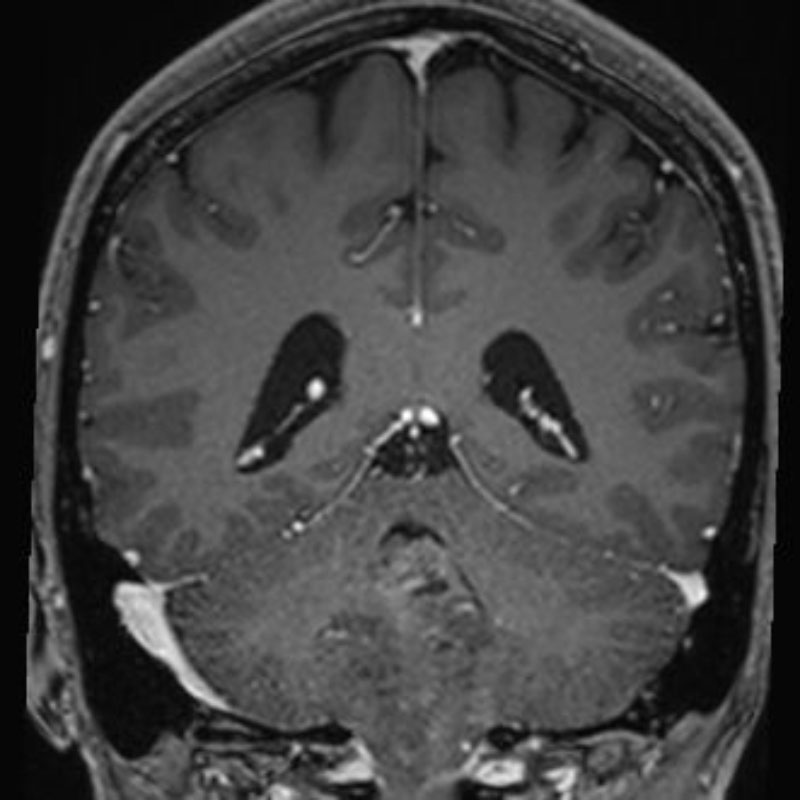

No.’25_102 手術前1

No.’25_102 手術前2